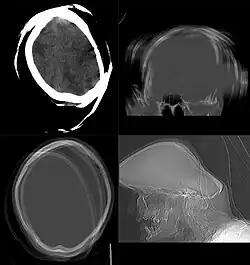

Head & Neck Imaging

CT scan remains the cornerstone imaging modality for the initial evaluation and subsequent management of patients with acute traumatic brain injury due to its rapid acquisition time and high sensitivity for detecting hemorrhagic complications, such as intraparenchymal hematomas and subdural hemorrhages.[56] CT scan of the head is typically used to detect infarction (stroke), tumors, calcifications, haemorrhage.[57] Tumors can be detected by the swelling and anatomical distortion they cause, or by surrounding edema. CT scanning of the head is also used in CT-guided stereotactic surgery and radiosurgery for treatment of intracranial tumors, arteriovenous malformations, and other surgically treatable conditions using a device known as the N-localizer.[58][59][60][61][62][63]